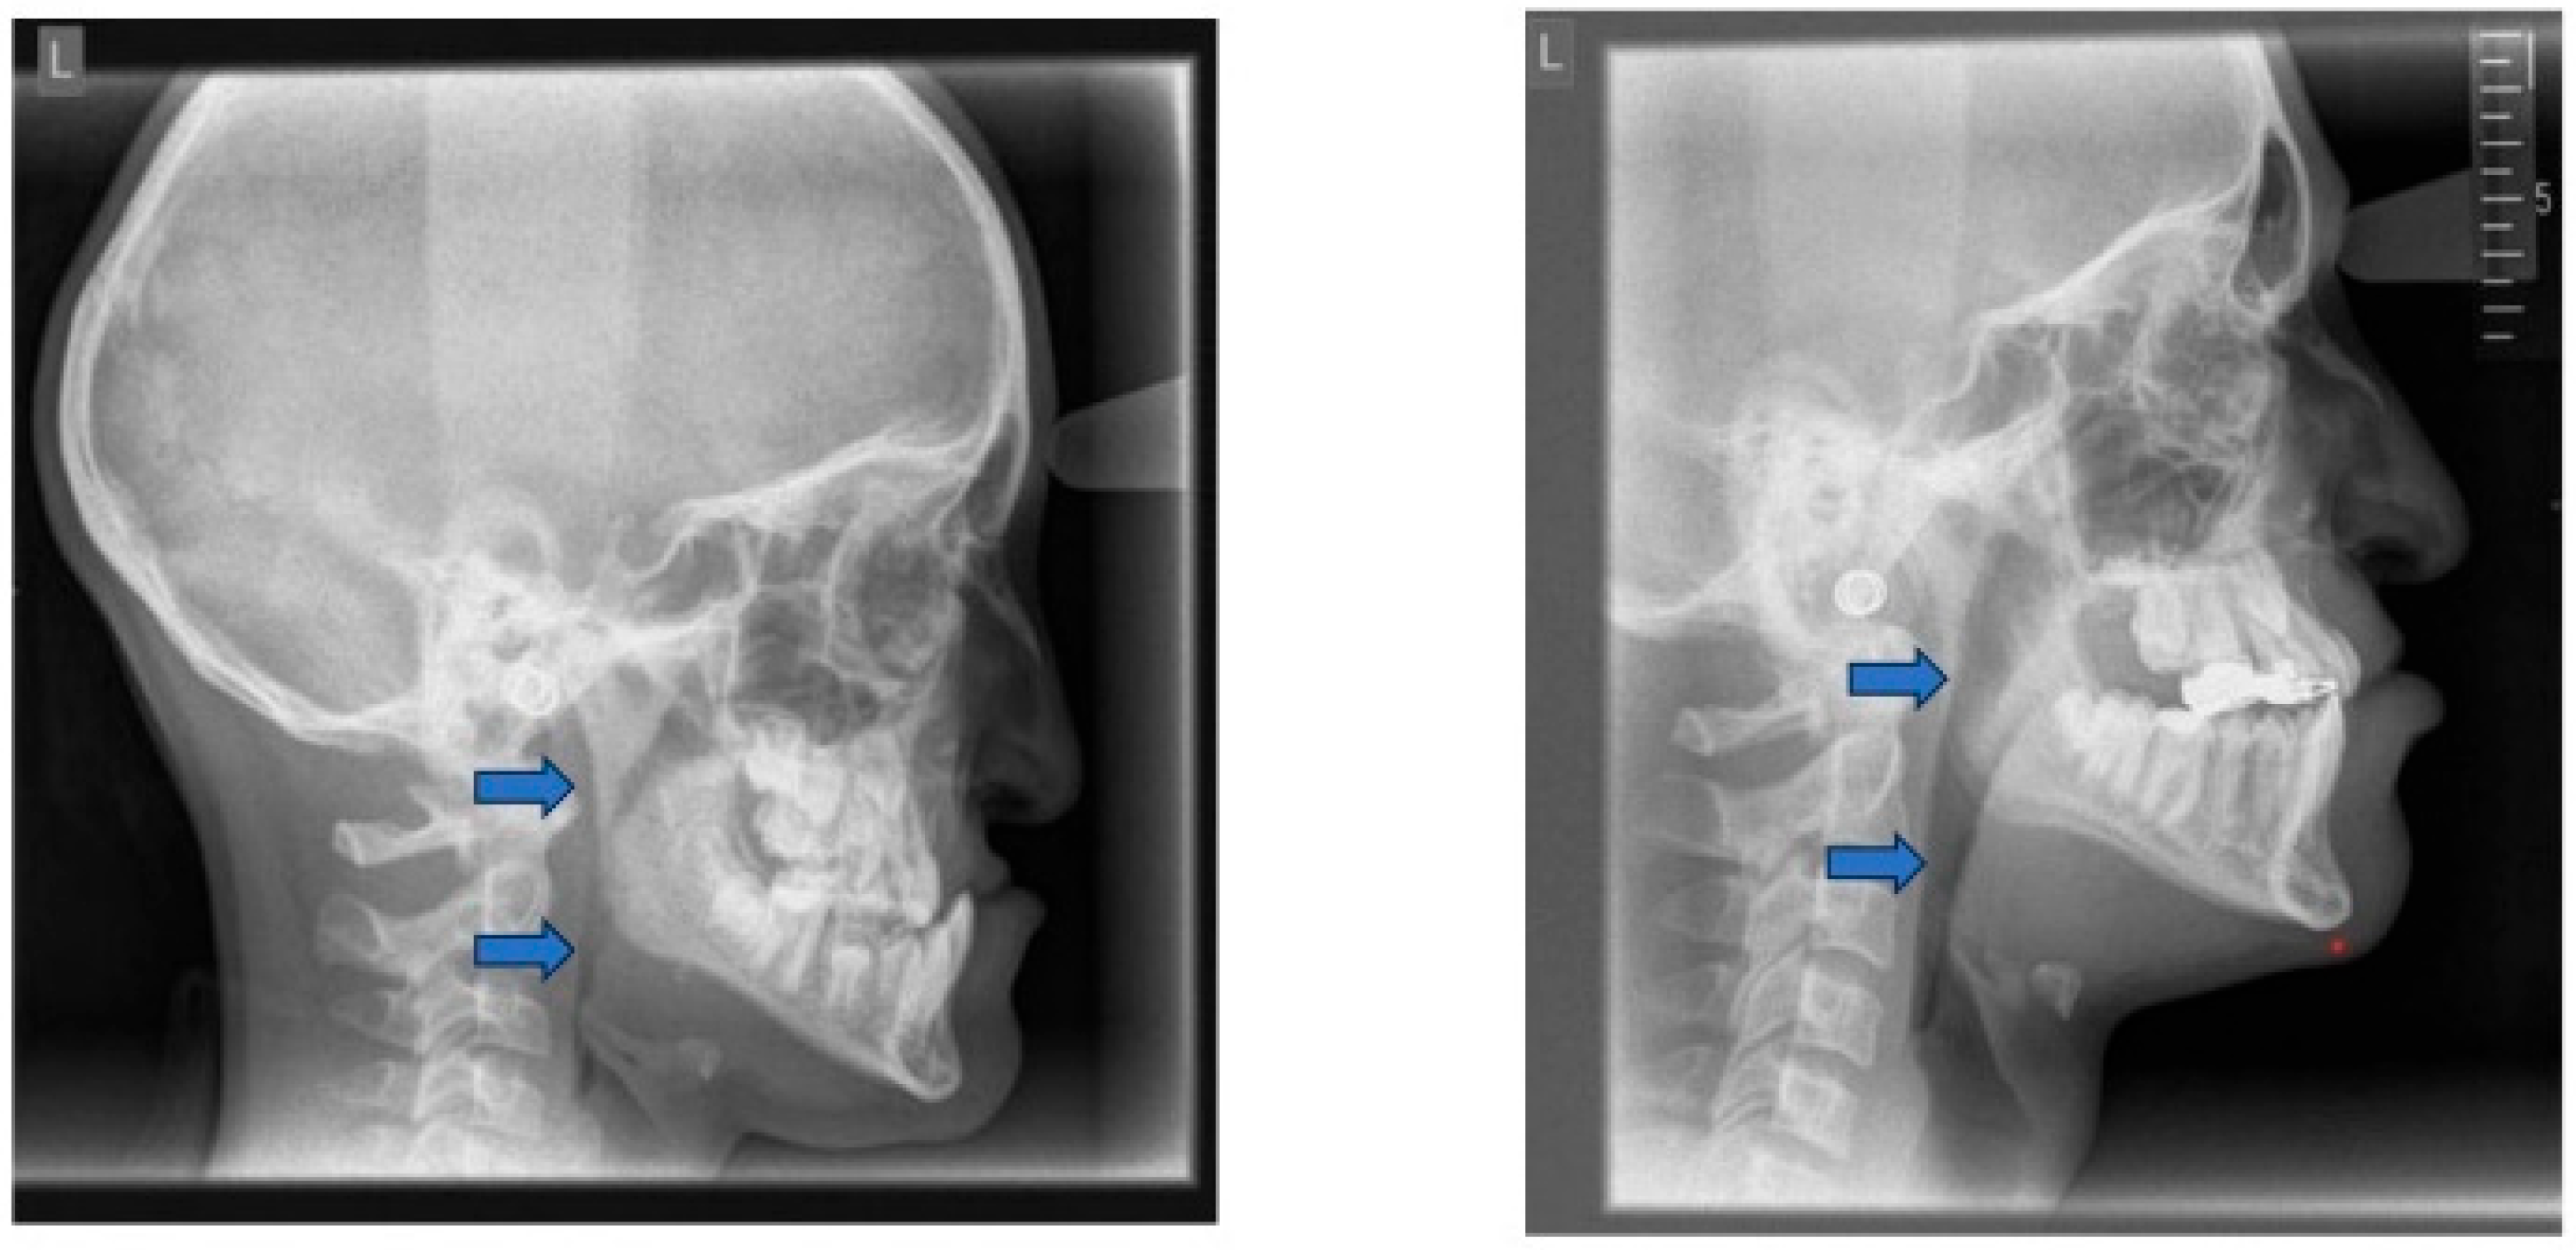

Lateral cephalometry allows for systematic assessment of craniofacial structures, including both hard and soft tissues. Furthermore, it enables the evaluation of the sagittal dimension of the posterior airway space (PAS) and can therefore serve as a screening tool [101,102]. This diagnostic tool is reproducible, affordable, easily accessible in an orthodontic office, involves minimal radiation exposure, and is non-invasive [2] (Figure 6). The cephalometric radiographs are taken in an upright and natural head position, where the eyes focus ahead with a horizontal visual axis parallel to the floor (Frankfort horizontal plane). The occlusion should be the habitual bite (not forced into maximum intercuspation) and the lips in gentle contact (not forcefully closed).

Nevertheless, it is essential to note that the soft tissues in the upper airway behave differently when a person is asleep, in a supine position, compared to an upright position [103,104,105,106]. Several studies attempted to establish a relation between airway dimensions and craniofacial structures in subjects with OSA through cephalometric assessment [107,108,109].